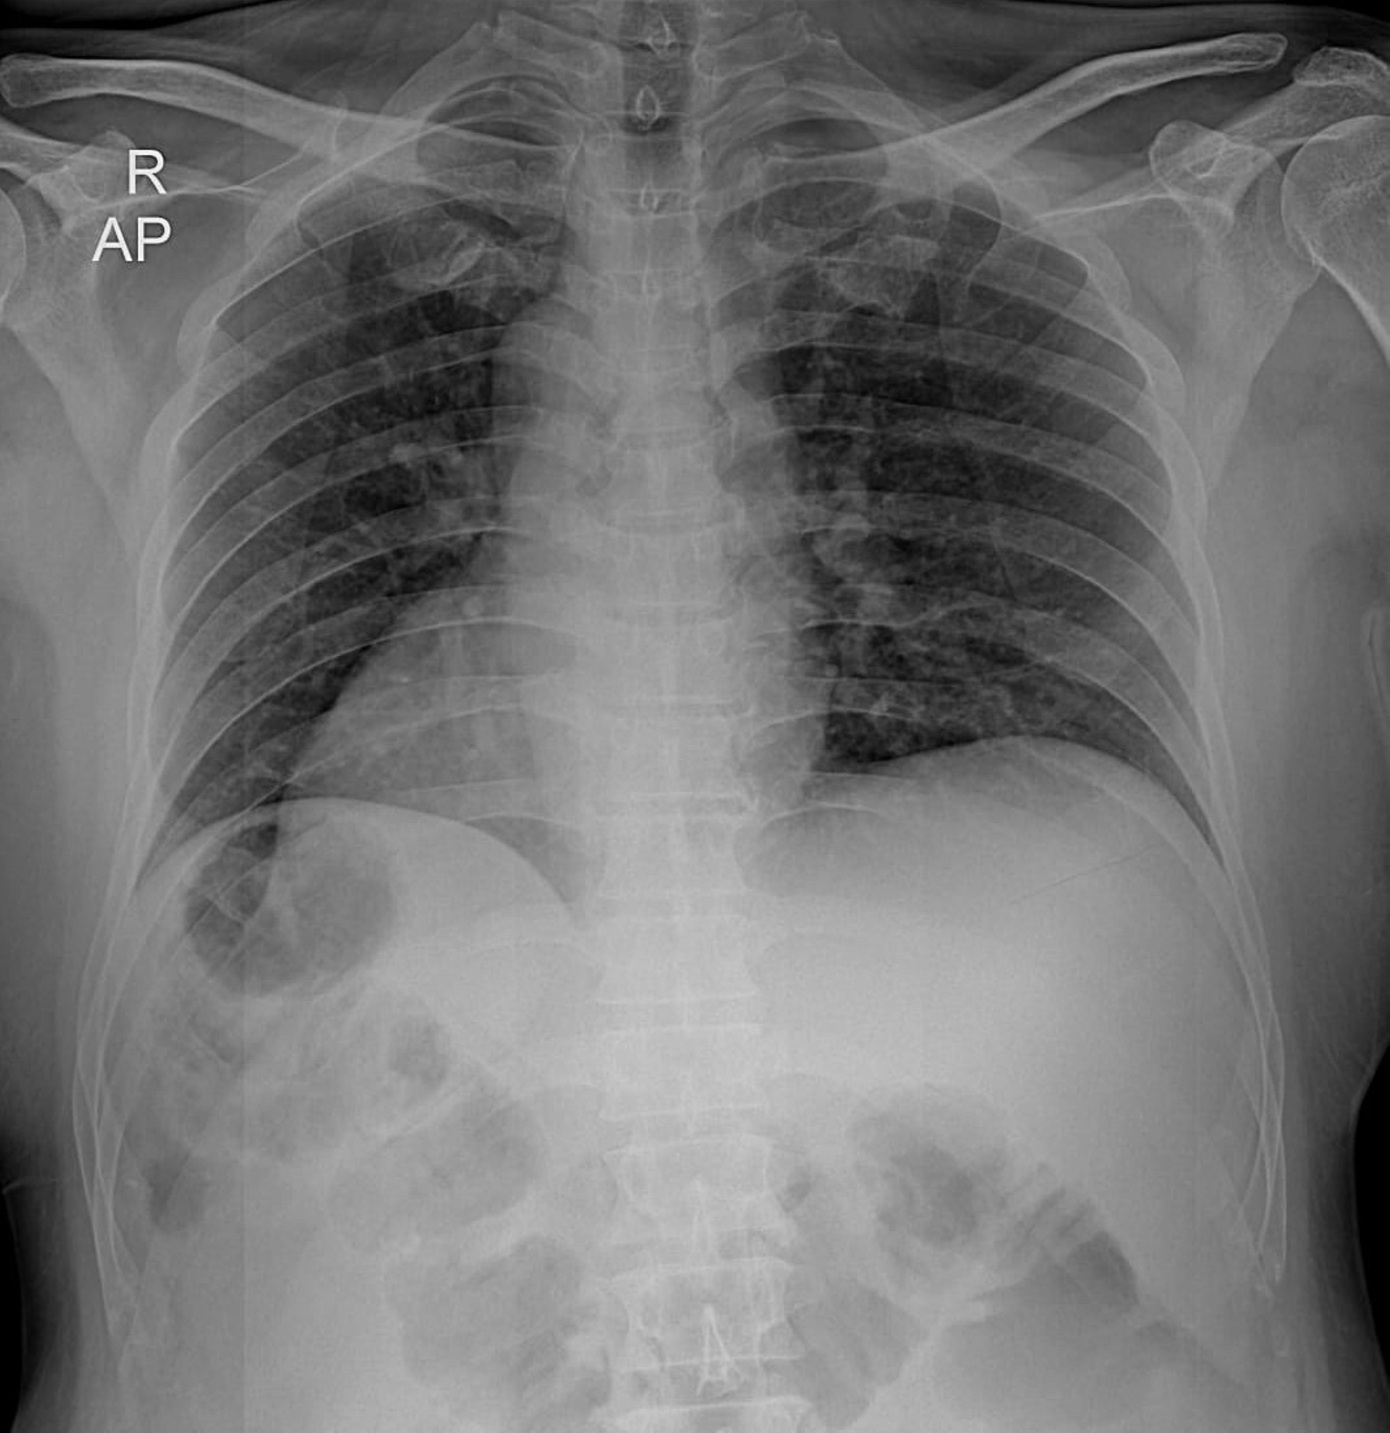

Πρόκειται για μια σπάνια συγγενή ανωμαλία, κατά την οποία τα όργανα του θώρακα και της κοιλιακής χώρας βρίσκονται σε θέση κατοπτρική σε σχέση με τη φυσιολογική ανατομία, σύμφωνα με την Cleveland Clinic. Για παράδειγμα, ο σπλήνας μπορεί να βρίσκεται στη δεξιά πλευρά αντί για την αριστερή ή το ήπαρ στην αριστερή αντί για τη δεξιά.

Η πρωταγωνίστρια της ταινίας Home Alone και ο σύζυγός της, Μπο Γουέλς, υποβάλλονταν σε εξετάσεις για φυματίωση, στο πλαίσιο προϋπόθεσης για τη φοίτηση του γιου τους σε σχολή νοσηλευτικής. Τότε, ο γιατρός της ζήτησε να κάνει τυπικές εξετάσεις, όπως ηλεκτροκαρδιογράφημα και ακτινογραφία θώρακος, κατά την επίσκεψή της στο ιατρείο, όπως η ίδια είχε αποκαλύψει σε συνέντευξή της το 2021.

«Όταν ο γιατρός μάς είπε ότι η καρδιά μου βρισκόταν στη δεξιά πλευρά και ότι τα όργανά μου ήταν αντεστραμμένα, ο σύζυγός μου είπε αμέσως: “Όχι, το κεφάλι της είναι γυρισμένο ανάποδα“», είχε αναφέρει η Ο’Χάρα γελώντας.